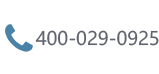

大脑里有个区域叫桥小脑角区,位置深、供血足、神经密布,医生管它叫"血腥三角"。蛛网膜囊肿最喜欢在这个角落安家,虽然是良性病变,但长到一定大小会压到听神经,处理不及时就会造成听力...